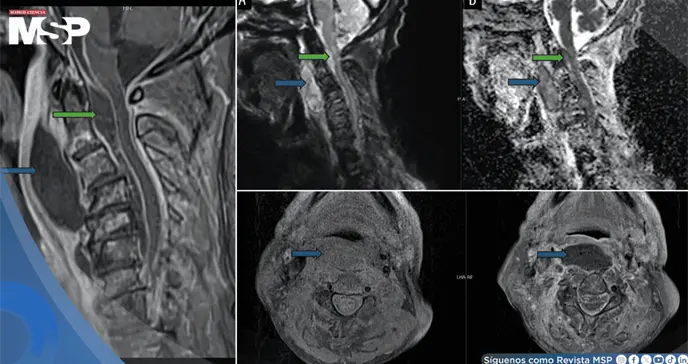

Para determinar la causa precisa de su condición, se realizaron estudios de imagen urgentes. Una tomografía computarizada y una resonancia magnética con contraste de cabeza y cuello revelaron hallazgos alarmantes.

Se observó una inflamación masiva con extenso edema y múltiples colecciones de pus que se comunicaban entre sí. Esta infección afectaba el espacio retrofaríngeo y, de manera crítica, se extendía hacia el espacio epidural en forma de un absceso, comprimiendo la médula espinal a nivel de la unión entre el cráneo y la columna vertebral.